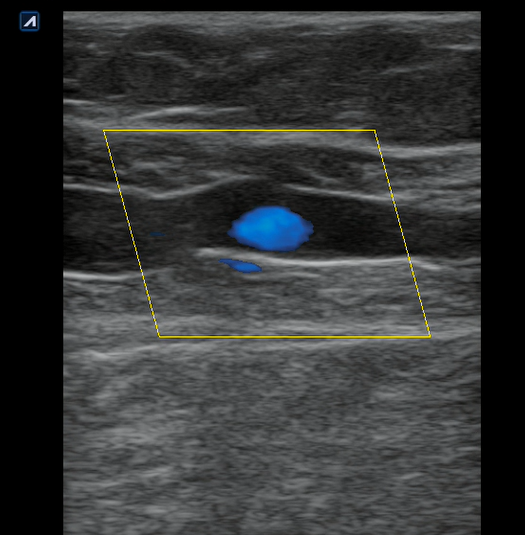

Se realiza ecografía clínica en consulta donde observamos a nivel inguinal adecuada compresibilidad de vena femoral y relleno con Doppler color. Cayado de safena libre y compresible. A 7 cm de distancia del cayado se aprecia, en territorio de safena, dilatación no compresible de la misma, contenido intraluminal ligeramente ecogénico y ausencia de Doppler color compatible con trombosis venosa superficial de 19 cm de distancia. Se estudia recorrido donde se observa en zona de dilataciones varicosas material ecogénico con ausencia de paso de Doppler alternando con zonas de paso parcial. En tercio distal de muslo comienza a desaparecer. Vena femoral profunda, poplítea y perforantes sin datos de trombosis.